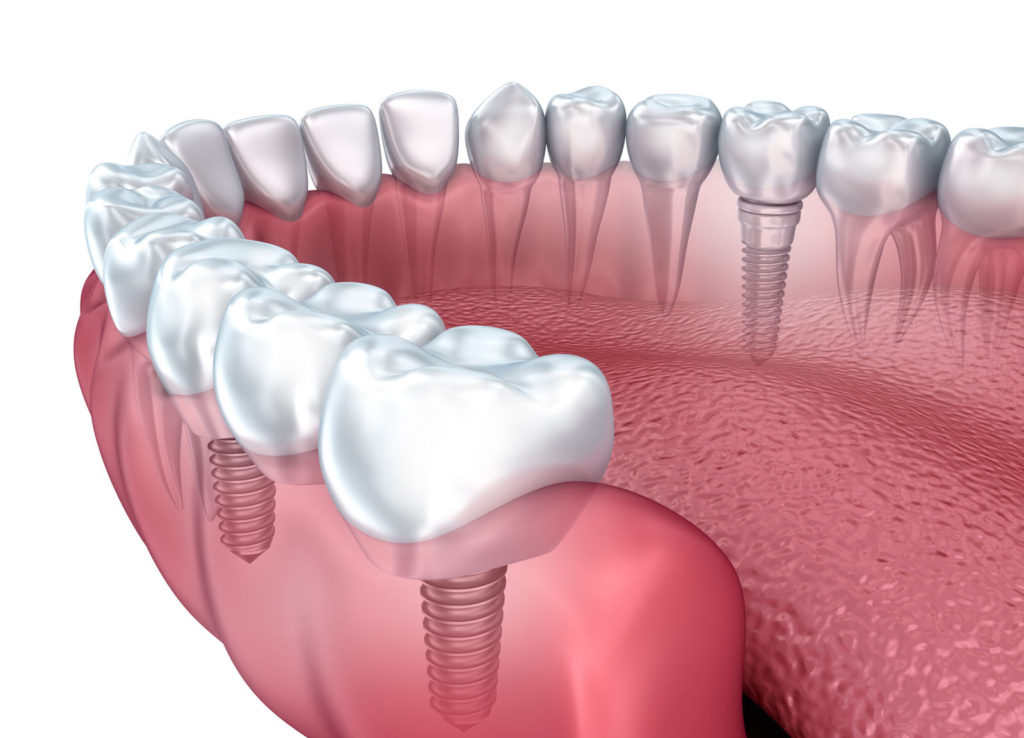

تركيب الأسنان الأمامية يمكن باستخدام زراعة الأسنان الثابتة للأسنان الأمامية في الأشخاص الذين فقدوا سن واحدة أو أكثر، حيث يتم وضع الغرسة جراحيا في فتحة في عظام الفك، وبعد أن تلتحم مع عظام الفك، وتعمل بمثابة جذر جديد للتاج الذي سيتم تركيبه، يتم تركيب التاج الذي سيحل محل السن المفقود، وهو ما يأخذنا للحديث عن أبرز المميزات التي يتم توفيرها من الزراعة في تركيا وهي كما يلي:

مرحلة التجهيز والتحضير

يجهز الطبيب الأماكن المعدة للزرع من خلال الحفر في عظمة الفك، بعد إعطاء المريض حقنة التخدير الموضعي أولا، ثم يتم إدخال الغرسات المصنوعة من التيتانيوم الخالص في عظم الفك مكان السن المفقود، ويتم إلصاق التيجان المؤقتة بها.

مرحلة الالتئام

يقوم الطبيب خلال هذه المرحلة بترك المريض لفترة من الوقت، ليتسنى التئام والتحام العظم الفكي، الموجود بين عظم الفك والغرسة واستيعاب الغرسات في مكانها، وتقدر هذه المدة بحوالي ثلاثة أشهر تقريبا للفك السفلي وستة أشهر للفك العلوي.

مرحلة التركيب النهائي

يخضع المريض خلال هذه المرحلة لعدة جلسات ضرورية، للوصول إلى التركيبة النهائيّة من التيجان، تتمثل بأخذ طبعات للفم وأخذ القوالب الخاصة للجذور المغروسة والأسنان الطبيعية الأخرى، ويفضل أن تصنع التيجان من مادة الزيركون لأن لونها طبيعي، وبعد الانتهاء من تحضير التيجان ويجب القيام بتجربة التركيبة النهائية قبل عملية تثبيتها بشكل نهائي للتأكد من ملائمتها.

تبدأ العملية بانتزاع السن المنخور أو المعطوب أو المكسور برفق وبأقل ضررٍ ممكنٍ للفك والأنسجة المحيطة، ومن ثم فحص مكان السن المخلوع وتنظيفه وتعقيمه بعدها يزرع الطبيب أساس السن الجديد في الفك بقوة دورانٍ كبيرة تضمن ثبات الأساس الجديد وبالتالي ثبات السن بعد ذلك بقية العمر، وعندها يتمكن الطبيب من تركيب تاج أو غطاءٍ أو وجهٍ مؤقتٍ للسن فوق ذلك الأساس قد يكون الأساس غير ثابت تماما وبالتالي يلجأ الطبيب عندها لجسر من الأسنان وهي رؤوس أسنان صناعية متصلة ببعضها توضع على المنطقة المصابة كلها.

غالبا ما يحتاج الفك إلى زراعة بعض العظام حول الأساس في عملية زراعة الأسنان الفورية وذلك لضمان ثبوتية الأساس ولحشو أية فراغات موجودة بينه وبين عظام الفك وتغطيتها بعد ذلك بغشاءٍ حيويٍ يحميها ويحفز نمو العظام وارتباطها بالأساس.